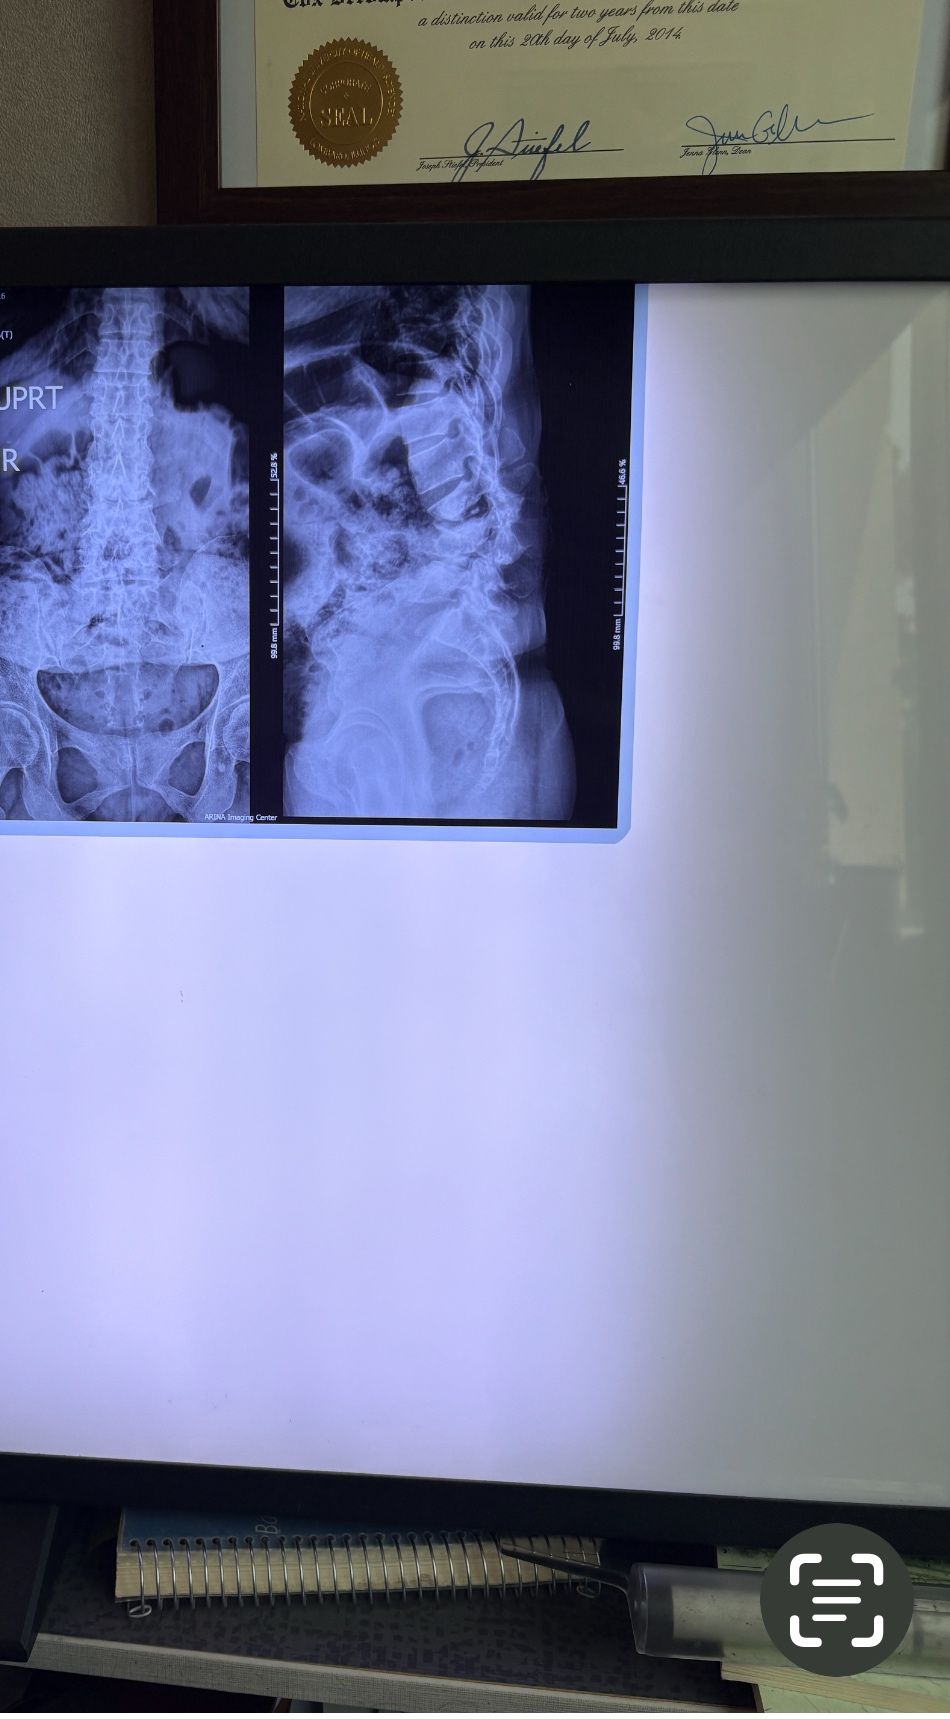

This time presented to my cl with LBP mainly during sleep at night. Just brought me her mri. According to her mri I ordered dynamic L/S X. R.

I didn’t accept her to give treatment. I referred her to her surgeon. What are your findings in her mri and X. Rays?

Is ant listhesis of L4 unstable or stable?

From several compression fractures we see which of is acute/ subacute and which ones are chronic fx?